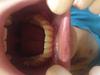

Нижние и верхние:)

И ВЧ и НЧ

Поставили 2 дня назад на НЧ. Все щеки разодраны, жевать больно. В общем жизньболь:(